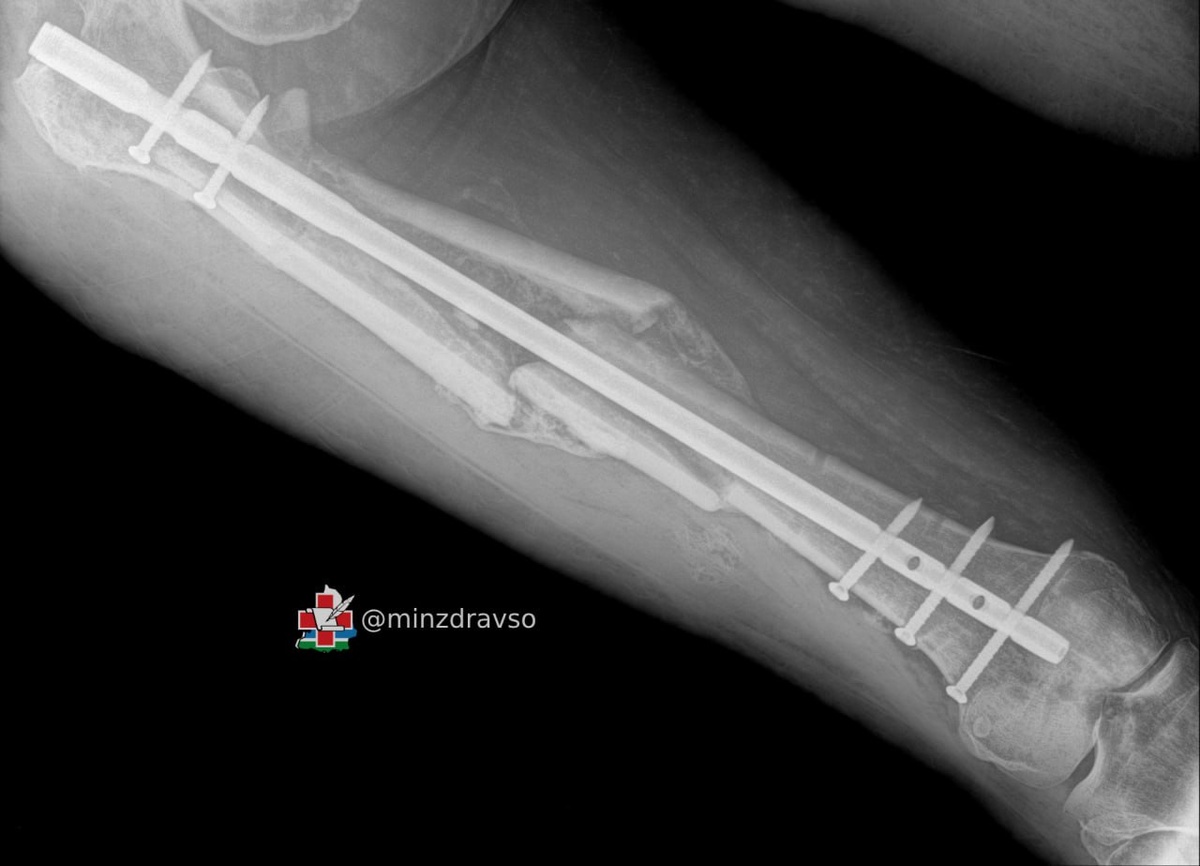

🪂Свердловские врачи поставили на ноги женщину, выпавшую с четвертого этажа

50-летнюю пациентку спасли специалисты нескольких отделений Верхнепышминской центральной городской клинической больницы. У женщины были тяжелые травмы таза и бедра, которые сопровождались массивным внутренним кровотечением с большой кровопотерей.

😱В больничных стенах женщина провела 120 дней. За это время пациентке провели пять сложнейших операций на тазовом кольце и бедренной кости. Когда она была подключена к аппарату ИВЛ, специалисты круглосуточно боролись за ее жизнь, проводили этапное оперативное лечение и многократные повторные гемотрансфузии — за это время ей перелили около 5 литров компонентов крови. Ситуация усугублялась большой массой тела женщины из-за ожирения II степени, которое негативно сказывалось на состоянии свердловчанки.

Травма таза традиционно считается одной из самых сложных областей травматологии в связи с высокими рисками для жизни и здоровья пациентов и технической сложностью оперативных методов лечения